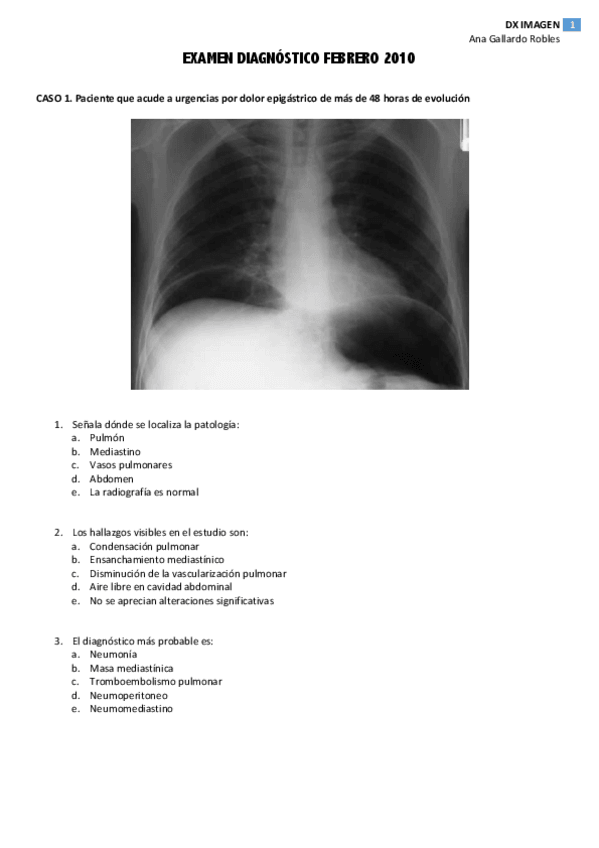

Exámenes - 2009-2010 Imágenes.pdf

29 páginas